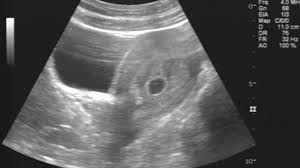

▶ 초음파에서 태아가 눈에 띄게 보이기 시작하는 시점은 보통 임신 6~7주차입니다.

하지만 개인마다 배란일이나 착상 시점 차이로 ±1주 정도 차이가 날 수 있어요. 그래서 생리 예정일이 지나고 2주 후쯤 산부인과를 방문하면 정확하게 확인할 수 있어요.

▶ 임신이 시작되었는지 빨리 확인하고 싶다면 임신4~5주차에 확인하세요. 임신낭이 보이는데 태아 자체보다는 임신이 시작되었음을 나타내는 첫 신호입니다.